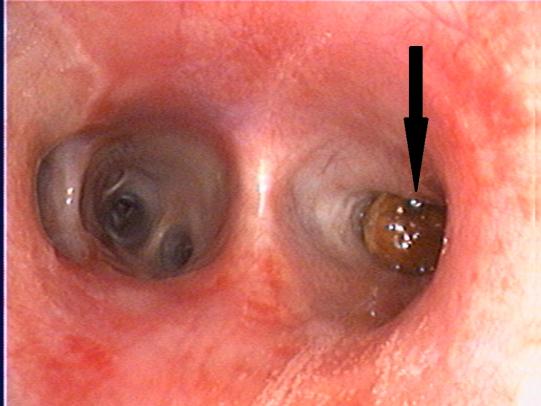

Migo wird narkotisiert - so können wir mit einem Endoskop die Atemwege untersuchen: Die Luftröhre ist stark gerötet und enthält viel Schleim. Wir trauen unseren Augen kaum: In einem Bronchus, kurz nach der Aufzweigung der Luftröhre in die sogenannten Stammbronchien steckt ein kleines, braunes, kugeliges Gebilde! Dieses Kügelchen wird jedesmal, wenn der Hund hustet, wie eine Flipperkugel aus dem Bronchus in die Luftröhre geschleudert. Die Narkose wird vertieft, damit der Welpe nicht mehr hustet; und nach einigen Versuchen gelingt es uns, den Fremdkörper mit einer feinen Zange zu packen und an die Aussenwelt zu befördern: Migo hat einen Kirschenstein eingeatmet!